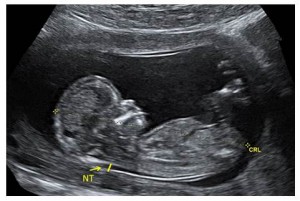

Nuchal Translucency (NT) Ultrasound

This ultrasound measures the clear (translucent) fluid at the back of the baby's neck. This pocket of fluid is also called the nuchal translucency (NT). It is normal for every baby to have some fluid at the back of the neck at this time.

When a baby has more fluid than what we typically see, it means there is a higher chance for the baby to have a genetic condition or another health issue.

This ultrasound can give you an accurate due date, and can tell you how many babies you are expecting. The ultrasound also looks at the baby's body parts, like the heart and the brain. The baby is still too small at this stage to be able to see the body parts in detail. There may be differences in how the body is growing and developing which cannot be seen at this time, but will be more obvious later in pregnancy at the 18-22 week (detailed anatomy) ultrasound